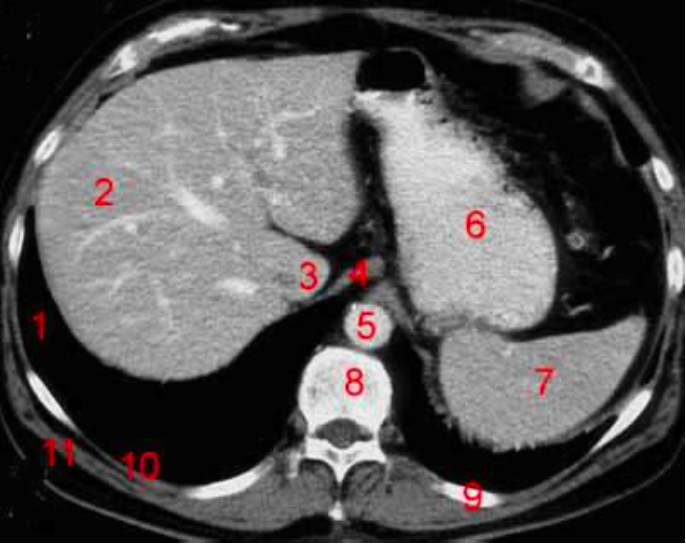

5

Number 3?

Gall bladder

6

Number 8?

Body of thoracic vertebra

7

Number 9?

Lt rib

8

Number 7?

9

Number 4?

Rectus abdominus

10

Descending colon

11

Number 2?

Rt lobe of liver

12

Number 10?

Rt rib

13

Head of pancreas

Spleen

Number 6?

Number 5?

L Ventricle